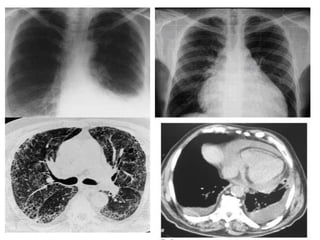

• PLEUROPULMONAR (más en hombres)

• Pleuritis con derrame pleural

• Fibrosis intersticial con alteración de la DLCO

• HT Pulmonar (raro).

• Bronquiolitis obliterante.

• Nódulos: cavitación, fístulas, neumotórax.

• Síndrome de CAPLAN: AR + neumoconiosis